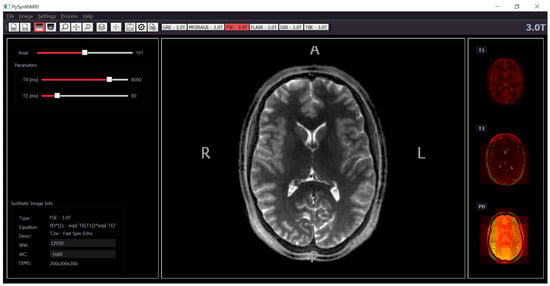

2.4. Graphical Interface Interaction

- Synthetic T1-weighted images simulating GRE (Gradient-recalled Echo) were synthesized with the following equation, incorporating the input maps of PD and T1 and setting the simulated acquisition parameter TR:

- Bias-free T1-weighted MPRAGE was synthesized by taking into consideration that B1 bias in QTI is incorporated in the PD map, which can be excluded from the formula, achieving a similar appearance to MP2RAGE uniform imaging [15]:

- Synthetic T2-weighted images simulating a SE (Spin Echo) acquisition were obtained as follows:

- Synthetic T2-FLAIR was obtained with a user-modified formula incorporating a coefficient TSAT, which enables the introduction of T1-weighting, which better mimics the one in conventional imaging:

- Synthetic TBE acquisitions were obtained from the generic signal model, with the appropriate parameters TI, TR, TE: